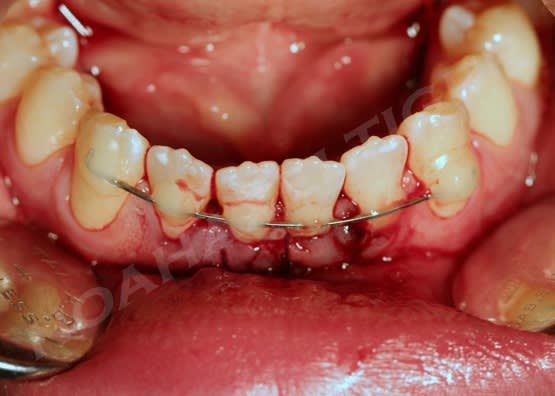

Patient de 20 ans venu en Urg cette après midi:

dent perdue temps moins de 2h

Suite à appel gardée en bouche

Bio réalisée dans une compresse stérile

Réimplantation après rinçage alvéole sérum Phy

Contention au Ribbond + compo , pas facile quand çà saigne

AB pendant 6 jours + Chx.

J'ai juste un doute en ce qui concerne l'hypochlorite , je ne m'en suis pas servi pour rincer le canal de peur de finir d'achever les quelques fibroblastes présents sur le cément du coup j'ai rincer le canal au sérum phy.

désolé pour l'ordre des photos